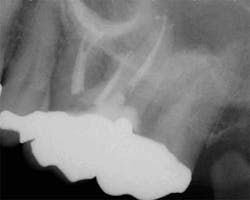

maxillary central incisor with a necrotic pulp. A prominent lateral canal can be seen,

but there is no way to know if multiple microscopic branches are present at any level

of the root canal system.